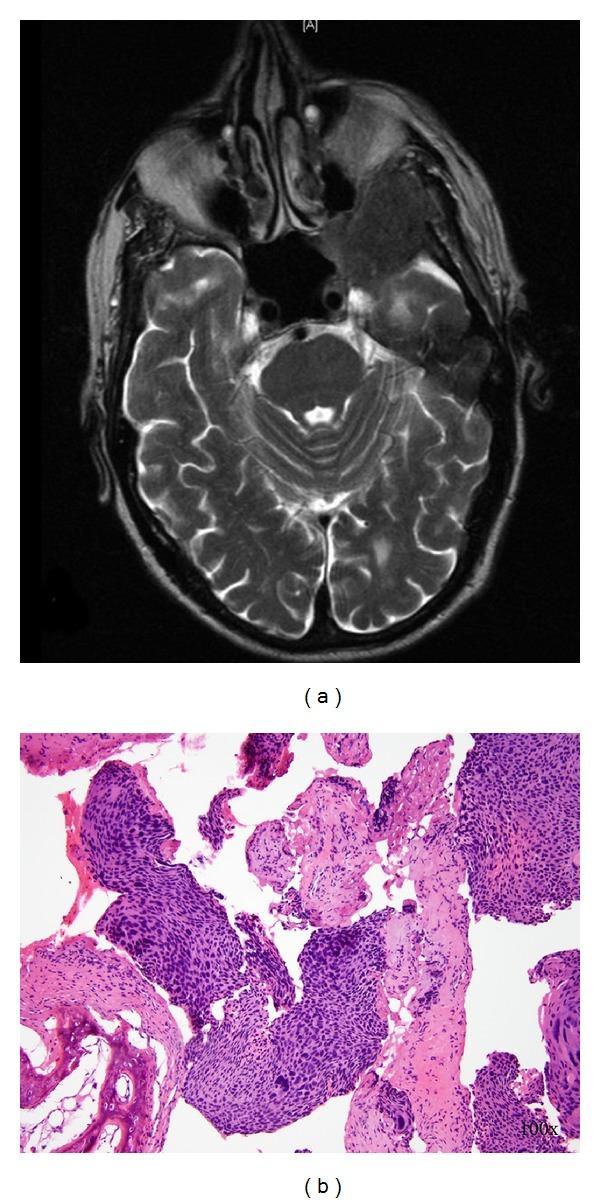

Squamous cell carcinoma of the anus is a relatively uncommon GI malignancy. When it does occur, it metastasizes in only a small minority of patients. Spread of anal squamous cell carcinoma to the brain is exceedingly rare, and has been previously reported only three times in the medical literature. We report the case of a 67 year old male who was diagnosed on presentation with a poorly differentiated anal squamous cell carcinoma that already had a solitary metastasis to the liver. While the tumors were initially responsive to chemoradiotherapy, the patient's primary and liver lesions recurred. The patient then underwent synchronous abdominoperineal resection for the primary lesion and a liver lobectomy for the metastasis. Soon thereafter, the patient developed focal neurologic symptoms and was found to have an intracranial lesion that on biopsy demonstrated metastatic squamous cell carcinoma. This case highlights the fact that patients with a previous history of anal squamous cell carcinoma can occasionally develop cerebral metastasis. Furthermore, cerebral metastases from anal squamous cell carcinoma portend a dismal prognosis even in the face of aggressive medical and surgical therapy.

肛门鳞状细胞癌是一种相对罕见的胃肠道恶性肿瘤。当它确实发生时,只有少数患者会发生转移。肛门鳞状细胞癌扩散至脑部极为罕见,此前医学文献中仅报道过3次。我们报告一例67岁男性病例,该患者初诊时被诊断为低分化肛门鳞状细胞癌,且已出现肝脏孤立转移灶。虽然肿瘤最初对放化疗有反应,但患者的原发灶和肝脏病灶复发。随后患者接受了原发灶的同期腹会阴切除术和转移灶的肝叶切除术。此后不久,患者出现局灶性神经症状,经检查发现颅内有一病灶,活检显示为转移性鳞状细胞癌。该病例凸显了既往有肛门鳞状细胞癌病史的患者偶尔会发生脑转移这一事实。此外,即使面对积极的药物和手术治疗,肛门鳞状细胞癌的脑转移预后也很差。